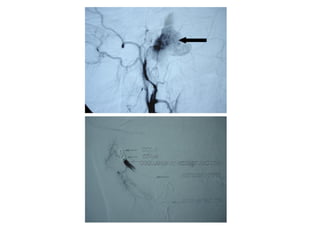

ANEVRYSMES CAROTIDE INTERNE

Dégénérescence de la couche élastique interne artérielle, du collagène combinée

à des modifications du flux sanguins (turbulences) conduisant à une dilatation de

l’artère.

L’anévrysme carotidien correspond à 2% des anévrysmes intra crâniens.

Traumatiques

Non traumatiques

Facteurs de risque: tabagisme, l’age et l’HTA, histoire familiale d’anévrysme,

maladie poly kystique rénale, dysplasie fibreuse et co arcation de l’aorte.

Délai de survenue: 5 jours à 9 semaines avec une moyenne de 7 semaines.

EPISTAXIS : SIGNE REVELATEUR

Diplopie, syndrome caverneux

GRAVITE: MORTALITE DANS 30% DES CAS.

DIAGNOSTIC:

SCANNER – IRM – ARTERIOGRAPHIE

Facteurs de risque de rupture:

Sexe féminin, anévrysme de plus de 1cm, multilobé , anévrysme symptomatique.

MISE EN PLACE

D’UN COIL.

LES COILS EN NEURORADIOLOGIE

INTERVENTIONNELLE.

Les coils sont des spires métalliques utilisées comme matériel d’occlusion

endovasculaire.

Les coils permettent le remplissage endovasculaire d’un compartiment vasculaire

relativement large (anévrysme intracrânien, sinus veineux dural, artère

cérébrale). Jusqu’au début des années 80, cela ne pouvait se faire qu’à l’aide de

ballonnets largables dont l’un des inconvénients majeurs était le dégonflage

précoce. Cet inconvénient n’existe pas pour les coils du fait de leur

structure métallique.

Tous les coils sont faits d’une tresse de platine. Le platine est en effet un métal

noble qui ne se corrode pas dans le courant sanguin et qui, par ailleurs, ne

détermine pas d’allergie.

Ces coils ont des formes diverses : hélicoïdales, sphériques, droites. Les coils

hélicoïdaux, qui sont probablement les plus utilisés, sont définis par le diamètre

de la spire (de 2 à 20 mm) et par leur longueur totale (de 10 à 500 mm).

Le principe est d’introduire un microcathéter à l’intérieur du sac anévrysmal

afin d’y dérouler des spires de diamètres progressivement décroissants.

On réalise ainsi une pelote métallique que l’on densifie jusqu’à ce que le

produit de contraste n’opacifie plus l’anévrysme sur l’artériographie de

contrôle.

Le nombre moyen de coils implantés par anévrysme est de 3,5.

coût: environ 700 €